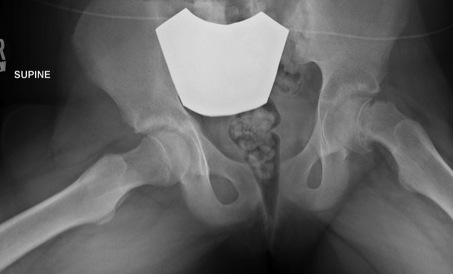

Frog Leg Laterals / Shoot through lateral

Shoot through lateral

- best to avoid frog leg lateral as may displace slip

Posteriorly displaced & angulated

Measure Southwick Angle

- calculate severity of slip

- also estimates risk of slip of other side / looking for retroversion